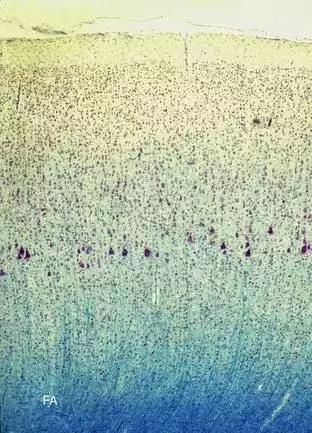

大腦材料可分為叫做灰質(zhì)和白質(zhì)兩類。灰質(zhì)看起來顏色較深,且由大腦神經(jīng)元的體細胞及其軸突和樹突組成。白質(zhì)是白色的,因為這些軸突通常包裹在髓鞘中,呈脂肪白。白質(zhì)之間的大塊主要由皮層神經(jīng)元的軸突組成。大腦皮層是像一個偉大的指揮中心。

我見過的反映這一概念最酷的插圖,由Dr. Greg A.Dunn and Dr. Brian Edwards.完成,讓我們看看灰質(zhì)皮質(zhì)的外層和它下面的白質(zhì)結(jié)構(gòu)之間的顯著差異:

神經(jīng)網(wǎng)絡(luò)